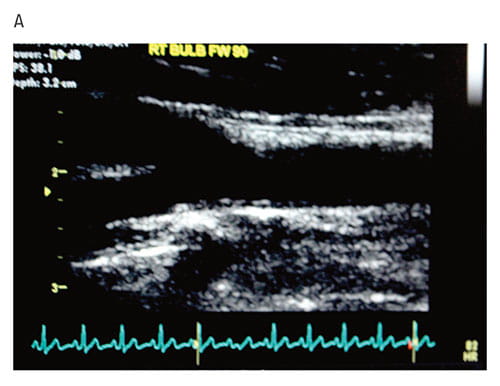

Urbina, first author Amy Shah, MD, MS, in the Division of Endocrinology, and several colleagues in the SEARCH for Diabetes in Youth Study evaluated 298 children with type 1 diabetes to measure how heart disease risk factors changed over five years. The team evaluated BMIz, lipids, blood pressure, hemoglobin A1c, and smoking status. They also used ultrasound to measure the carotid artery.